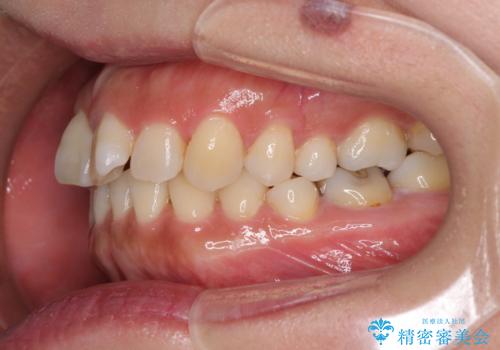

軽度な歯列不正 インビザライン・ライトによる矯正治療

- 上下前歯の叢生を気にして来院された患者様です。

費用を抑え、期間もあまりかけずに治療をしたいとのことで、インビザライン・ライトを用いて矯正治療を行うこととしました。